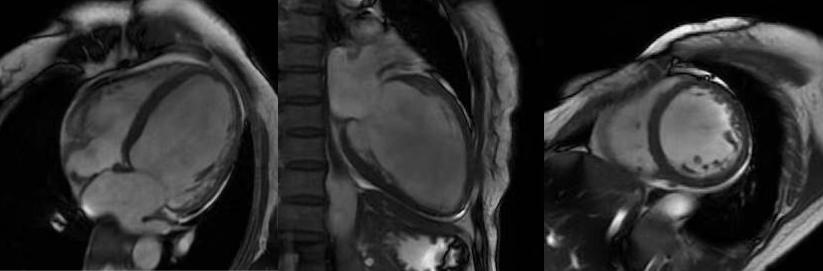

非缺血性心肌?。簲U張型心肌病、肥厚型心肌病、高血壓性心肌病、心肌淀粉樣變、心肌過度小梁化、限制性心肌病、心臟結(jié)節(jié)病、心肌炎等,心肌呈現(xiàn)不同程度條狀、斑片狀、斑點狀的延遲強化。

擴張型心肌病

肥厚型心肌病,舒張末期心尖形似“黑桃A征”